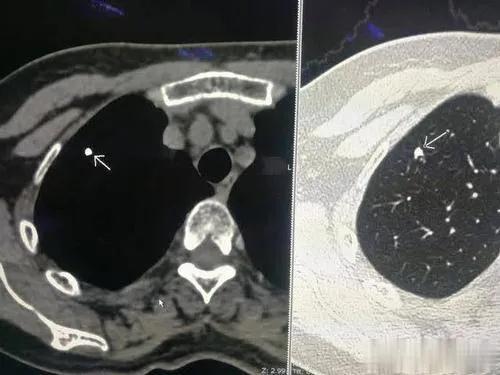

肺部結(jié)節(jié)是指在胸部影像學(xué)檢查中發(fā)現(xiàn)的直徑小于3厘米的球形病灶。肺部小結(jié)節(jié)是指直徑小于1厘米的球形病灶。

這是引起肺部結(jié)節(jié)最常見的原因之一。一個人曾經(jīng)患過肺炎,等到肺炎愈合之后(很多時候,患者自己可能都沒有感覺),在這個地方就會形成一個結(jié)節(jié),就相當(dāng)于我們的皮膚劃破愈合之后,會留下一個傷疤一樣。這種病灶通常還會有鈣化,就會顯得特別亮。這種情況下,人一般沒有任何癥狀,也沒有任何不舒服。

3、早期肺癌

如果體積大于1厘米,而且這個結(jié)節(jié)長得非常不好看——結(jié)節(jié)不規(guī)則,邊緣粗糙,有毛刺,那就是非常不好的信號,高度提示是肺癌。如果是這種情況,那么就要手術(shù)切除了。